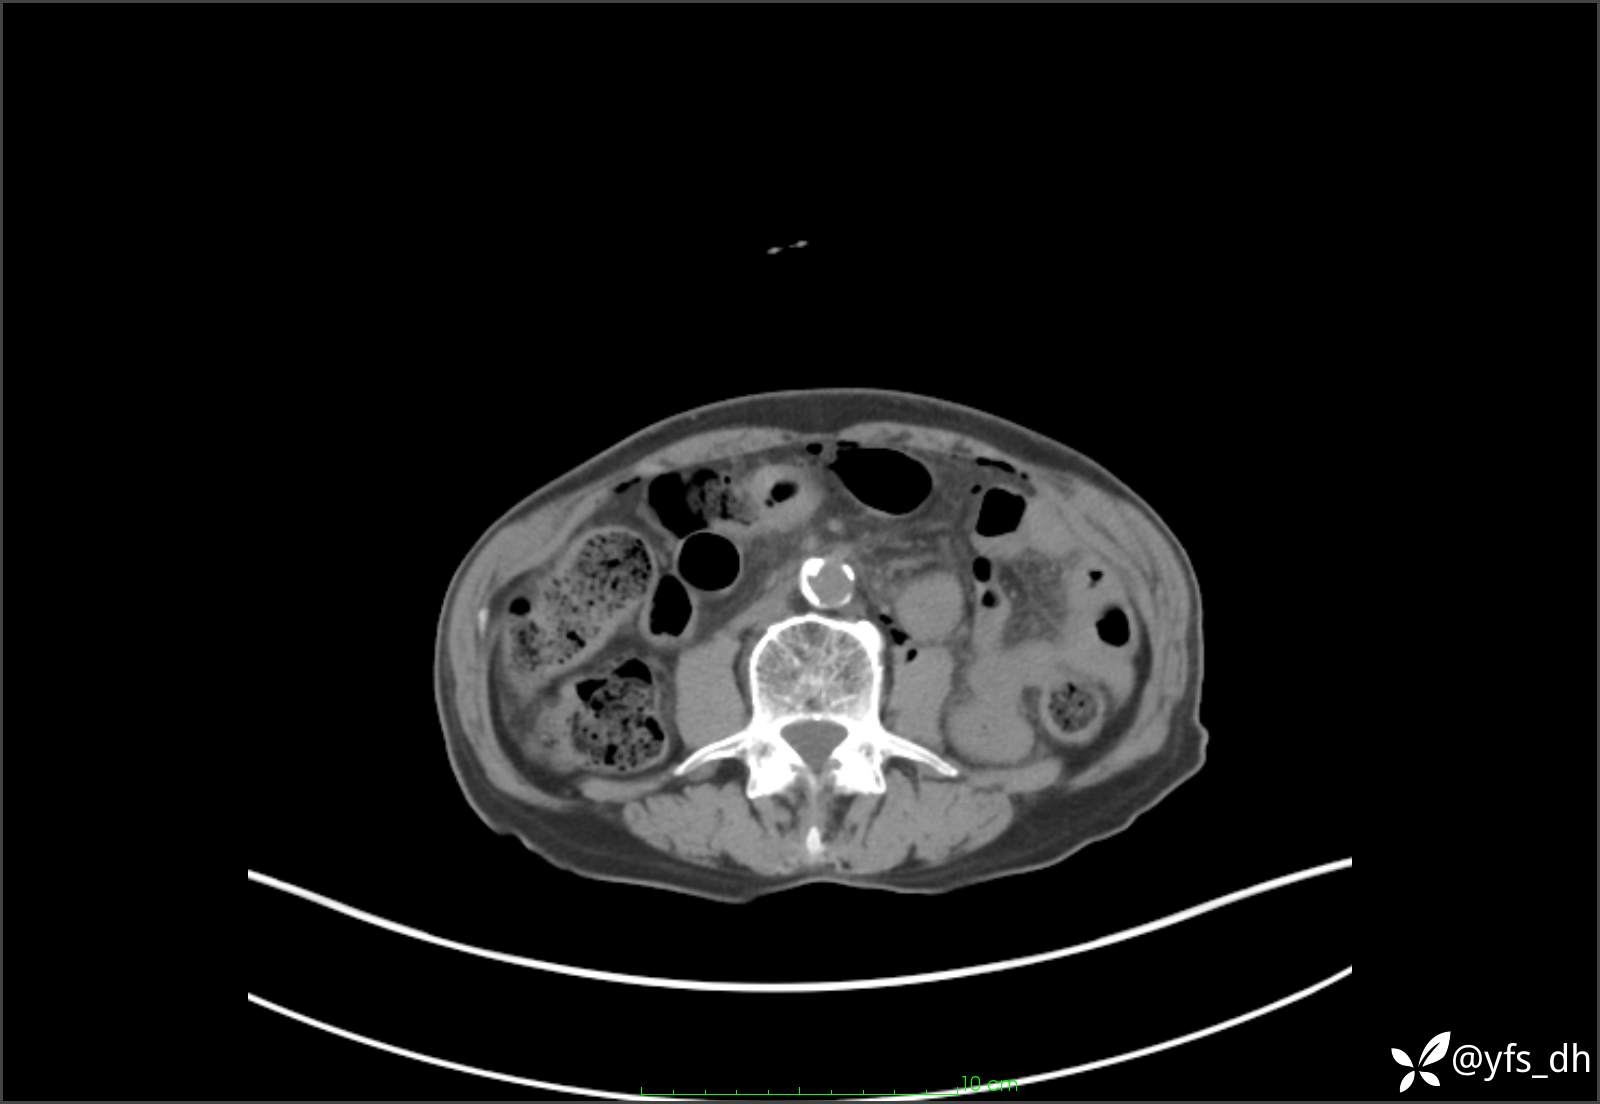

1.简要病史:患者4天前突发上腹部疼痛不适,但可以忍受。3小时前饭后突然加重,不能忍受后就诊。

2.简要手术记录:术中见腹盆腔大量肠液及粪便,乙状结肠中下段见一约3cm的破口。